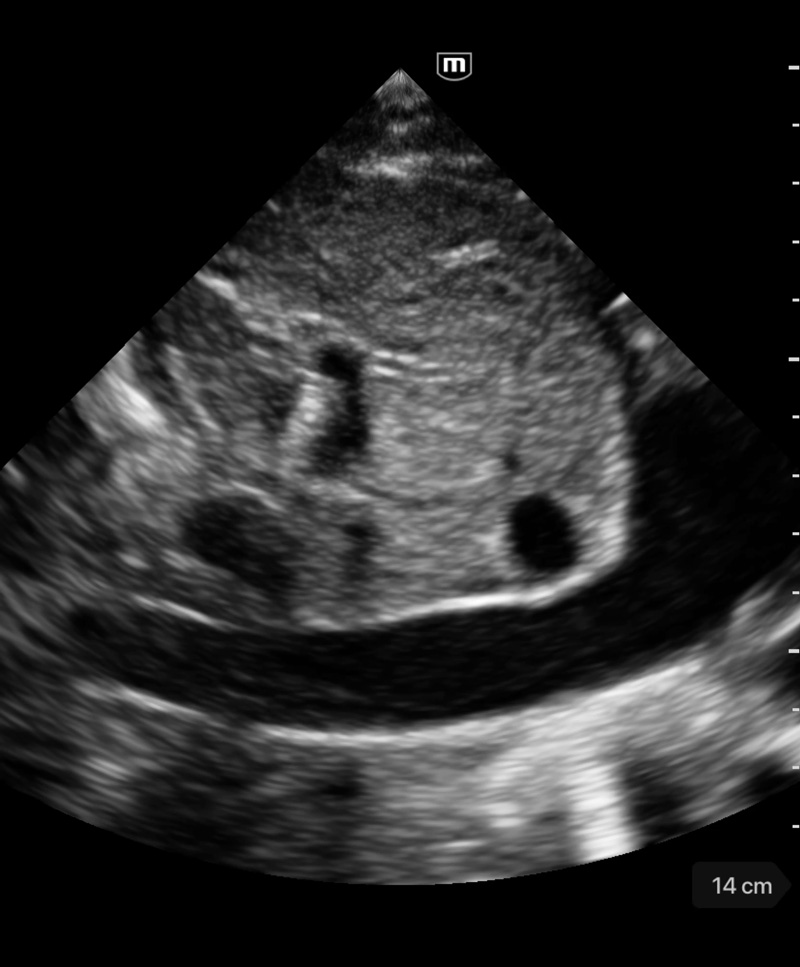

Immagini cliniche

Rigurgito mitrale e tricuspidale

Cardiomiopatia dilatativa

Immagini cliniche

Rigurgito mitrale e tricuspidale

Cardiomiopatia dilatativa